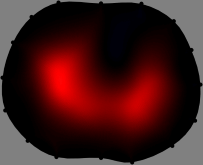

Figs. 3 and 4 compare the performance of the proposed FER method in (20) with the standard regularized least-squares method ((19) when \mathcal{R} is the identity matrix). The regularization parameter of the standard method was heuristically chosen for its best performance, and the parameter of the FER method was set to be one of three different values λ=0.05,0.2,𝜆0.050.2\lambda=0.05,0.2,\infty. The injection current was 1 mARMSRMS{}_{\tiny{\mbox{RMS}}} at 100 kHz, and the frame rate was 9 frames per second. The reference frame at t0subscript𝑡0t_{0} was obtained from the maximum expiration state. The measured data, 𝐕˙(tm)˙𝐕subscript𝑡𝑚\dot{\mathbf{V}}(t_{m}), represent the voltage differences between each time tmsubscript𝑡𝑚t_{m} and t0subscript𝑡0t_{0}. The blue regions, which denote where conductivity decreased by inhaled air, increased during inspiration and decreased during expiration. The FER method with λ=𝜆\lambda=\infty was clearly more robust than the standard method that produced more artifacts originated from the inversion process.

Figure 4: The reconstructed images of the conductivity change of the subject B by the standard regularized least square method and the proposed fidelity-embedded regularization (FER) method for three difference values λ=0.05,0.2,𝜆0.050.2\lambda=0.05,0.2,\infty. Here, the time step is 0.55 seconds (tm+5tm0.55subscript𝑡𝑚5subscript𝑡𝑚0.55t_{m+5}-t_{m}\approx 0.55).